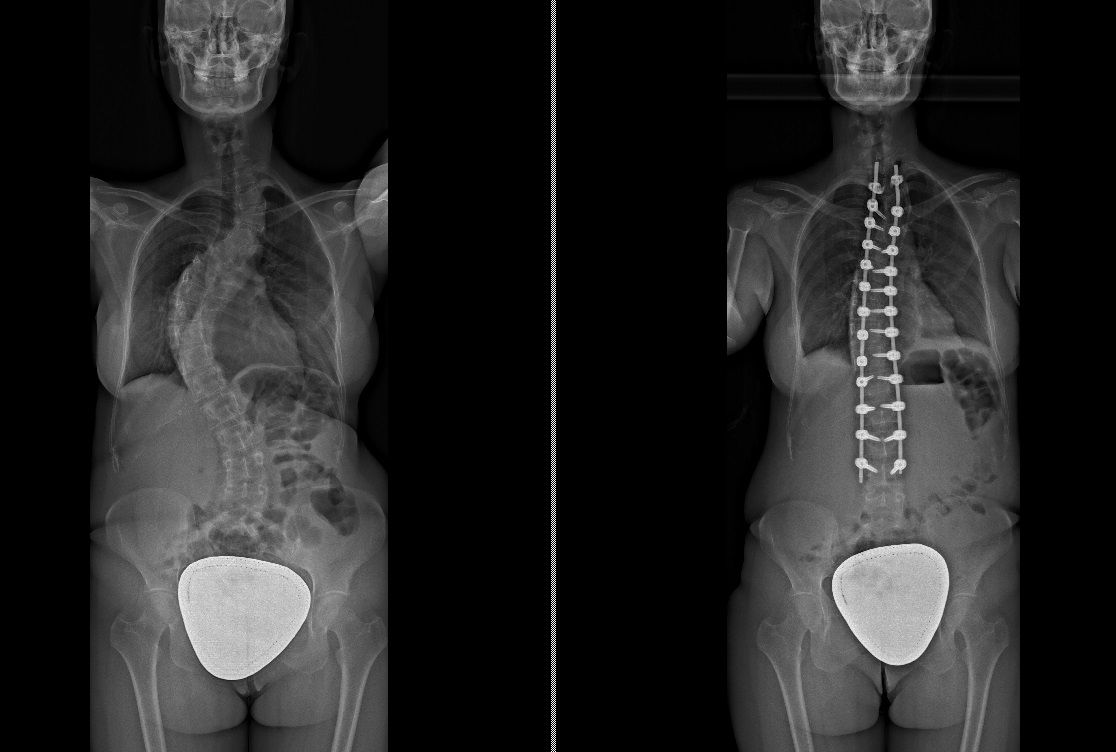

Foto e video